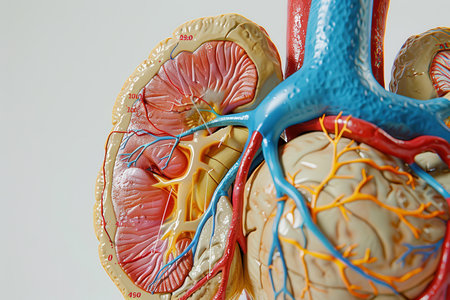

A close up of a pair of kidneys with red and orange blood vessels. The image is a representation of the human body and its internal organs

3D-printed kidney model on glass. Detailed renal cortex, medulla, ureter, vascular system. Red/blue resin highlights arteries/veins. Side lighting emphasizes printing texture. Blurred background: futuristic lab, holographic blood flow data. Advanced medical technology.